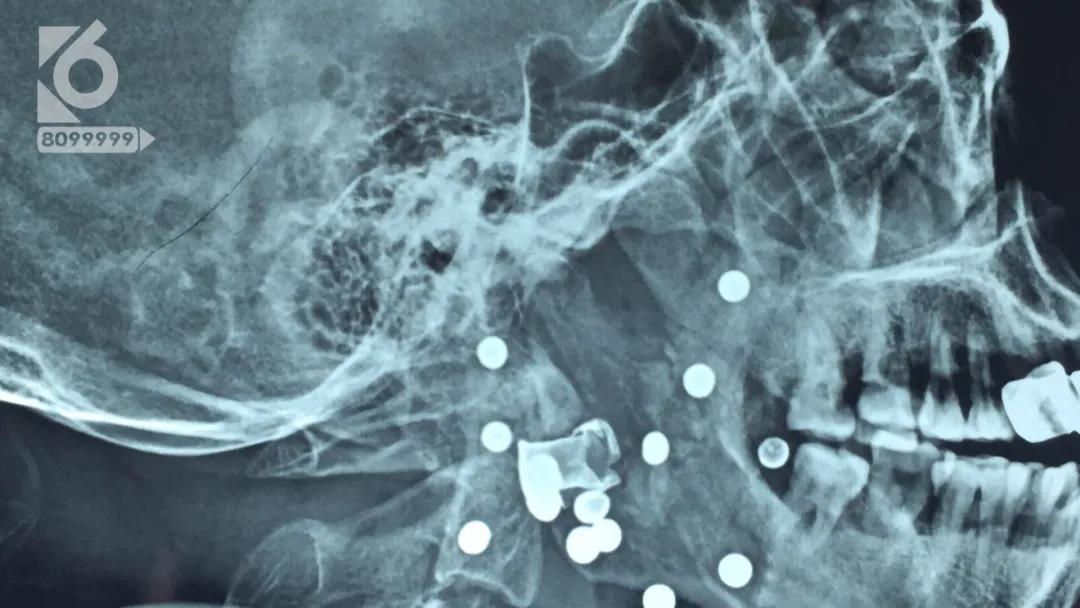

监控显示,男子被送抵医院时,整个头部都已经被包裹得严严实实,看不出具体受伤的情况。医生接诊后迅速对男子展开检查,而这一查,把医生都给吓了一跳。

男子的面部竟然嵌入了有十多颗钢珠,疑似遭到了枪击。

经过两个多小时的手术,共取出了十一颗钢珠和半个损坏的弹壳。

医生说:“一共十五颗半,十一颗半都取出来了,还有四颗在气管里太危险了,不能取了,最危险的弹壳取出来了,弹壳在动脉旁边呢。”